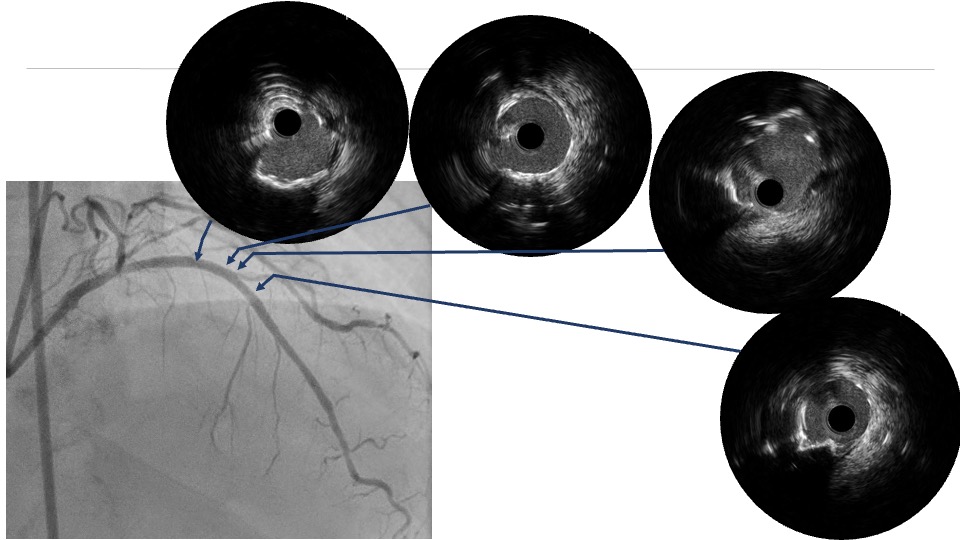

Coronary angiography via the radial approach showed a severe proximal LCx stenosis and a long, severe mid-LAD stenosis, while the RCA had no significant disease. IVUS of the LAD demonstrated diffuse calcification and an eccentric calcified plaque protruding from the septal side near the diagonal branch bifurcation. The guidewire was biased toward the diagonal branch, causing tenting of the relatively healthy wall at the most critical segment.

PCI was first performed for the LCx, using orbital atherectomy followed by cutting balloon predilatation and drug-coated balloon therapy with good angiographic result. One month later, PCI was attempted for the LAD lesion using a 8F system via right femoral approach. Intravascular ultrasound (IVUS) revealed a diffusely eccentric calcified plaque located on the septal side. While wire bias in the proximal segment was toward the calcified plaque, the distal segment showed tenting of the wire toward a plaque-free site on the diagonal branch side. At this point, we considered that debulking of the distal segment would be a high risk of vessel injury. We hypothesized that performing proximal segment debulking that had a favorable wire bias might shift the overall wire bias toward the septal side. Then Only proximal OAS was performed using pull-back ablation.Follow-up IVUS showed disappearance of distal tenting and favorable wire bias toward the calcified plaque. As a result, OAS was safely performed in the distal segment as well. Additional debulking of the residual calcified plaque was conducted with a 2.0 mm Rotablator. IVUS confirmed effective debulking without vessel injury in the area of concern. The entire lesion was then dilated with a CB; however, a dissection with hematoma occurred, and a drug-eluting stent (DES) was implanted. Final IVUS demonstrated acceptable stent expansion, and final angiography showed no residual stenosis or flow limitation.